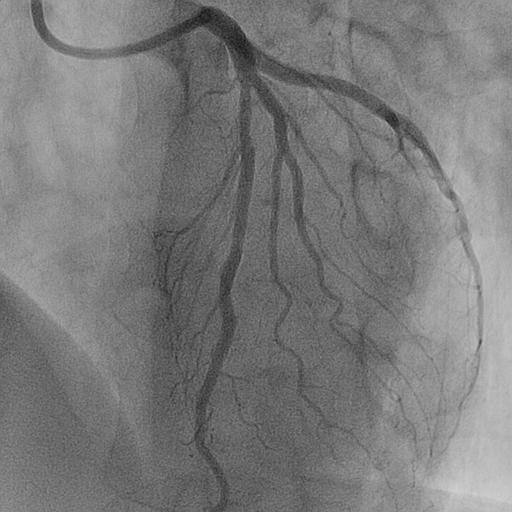

Coronary computed tomography angiography (CCTA) revealed a focal lesion stenosis in the mid-left anterior descending (LAD) artery, without significant disease in the remaining coronary vessels. Based on these findings, the patient was diagnosed with stable angina and referred for invasive coronary angiography to further characterize the lesion and determine the optimal revascularization strategy.

Relevant Catheterization Findings

Coronary angiography confirmed a hemodynamically significant stenosis in the mid-LAD, consistent with CCTA. OFDI revealed a high-intensity, heterogeneous signal with layered structure and microchannel formation, features suggestive of an organized thrombus rather than a lipid-rich atherosclerotic plaque. This morphology was considered to be associated with a low risk of plaque restenosis and favorable balloon response, making a stent-free strategy a reasonable therapeutic option.

The target mid-LAD lesion was initially treated with excimer laser coronary angioplasty (ELCA) to ablate thrombotic tissue and facilitate subsequent vessel preparation. Following laser irradiation, prolonged low-pressure balloon dilatation was performed to optimize lesion modification and achieve adequate luminal expansion. Subsequently, a paclitaxel-coated drug-coated balloon (DCB) was applied at the treated segment to deliver antiproliferative therapy without stent implantation. Final angiography showed satisfactory luminal gain with TIMI 3 flow, and no evidence of vessel recoil or major dissection. Post-procedural OFDI confirmed a well-expanded lumen with smooth vessel surface, and no significant residual thrombus or flow-limiting dissection. The patient was discharged on dual antiplatelet therapy for 3 months. At 2-year follow-up, CCTA demonstrated sustained vessel patency without restenosis, supporting the long-term durability of this stentless ELCA+DCB strategy.